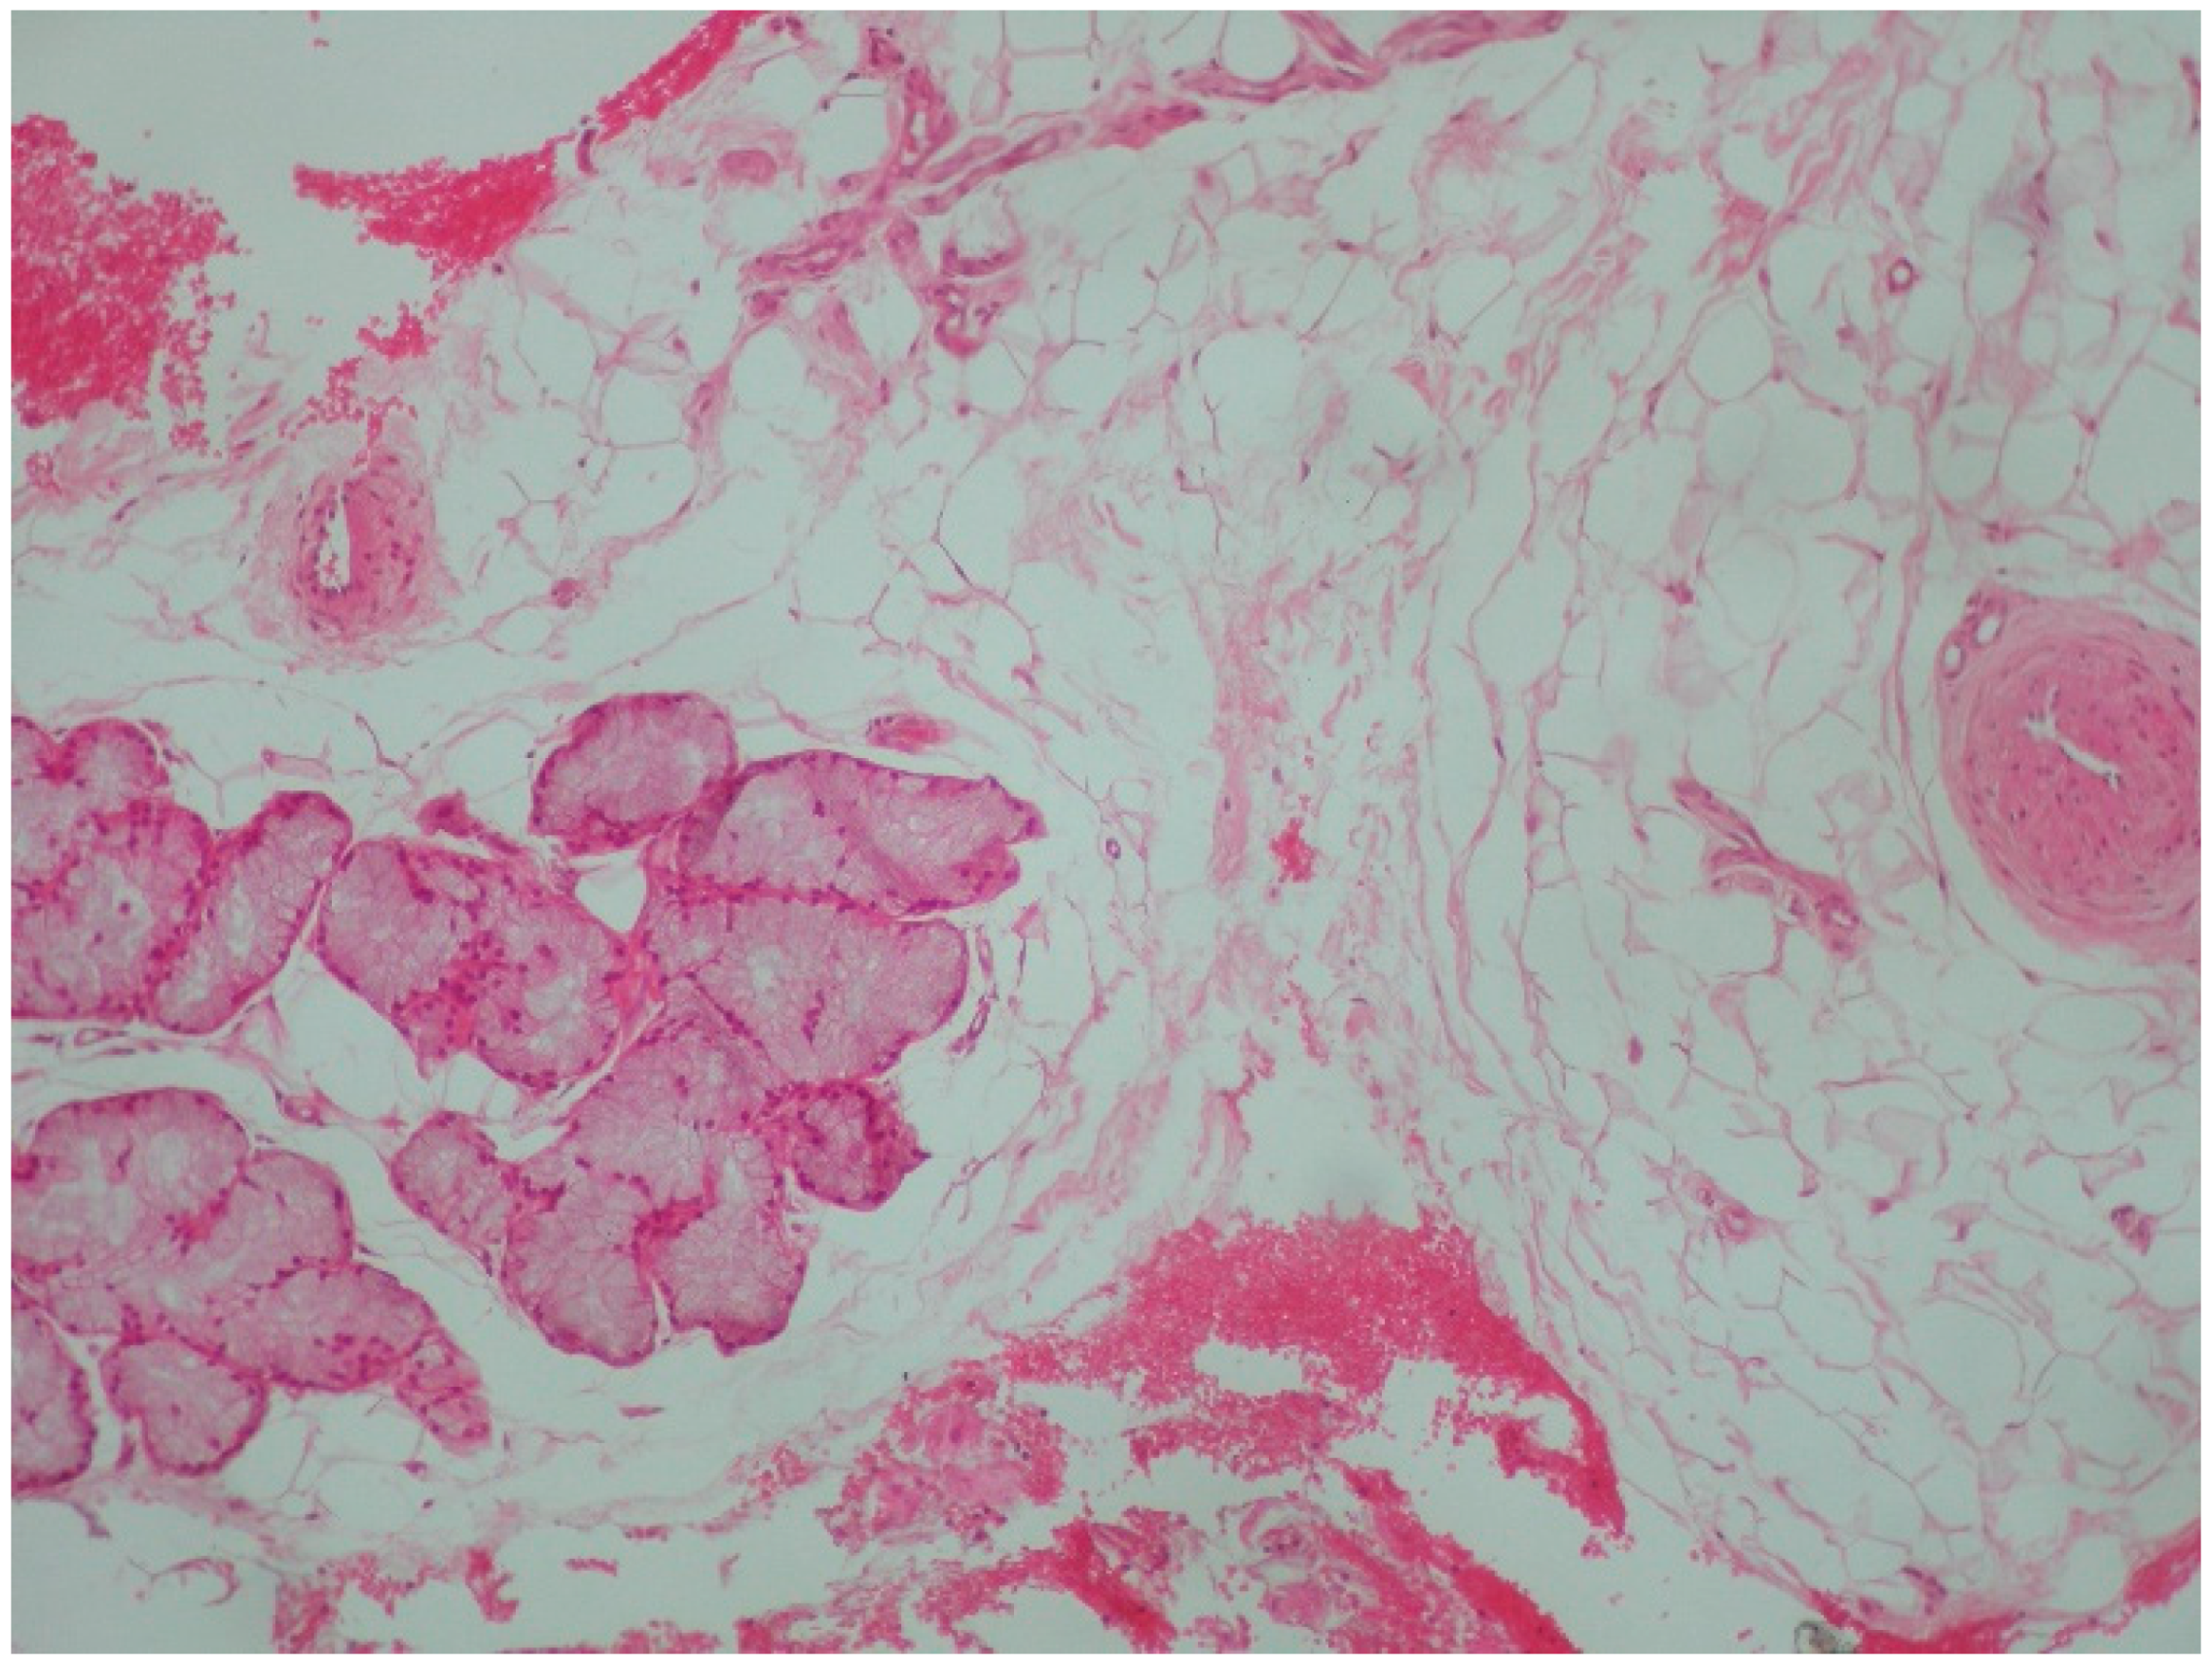

2. Case Presentation